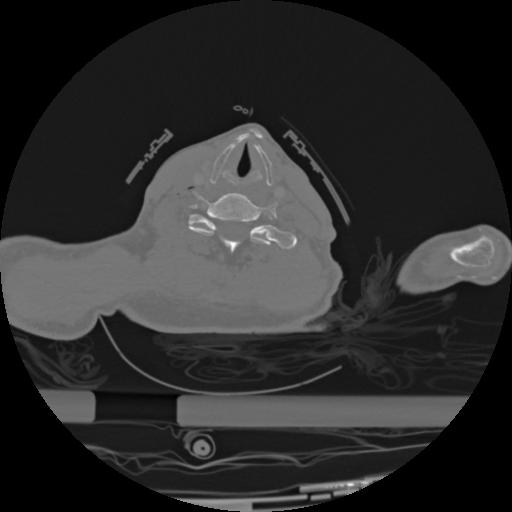

22 ANGIO,CE,Vol,0.5,ANGIO,,